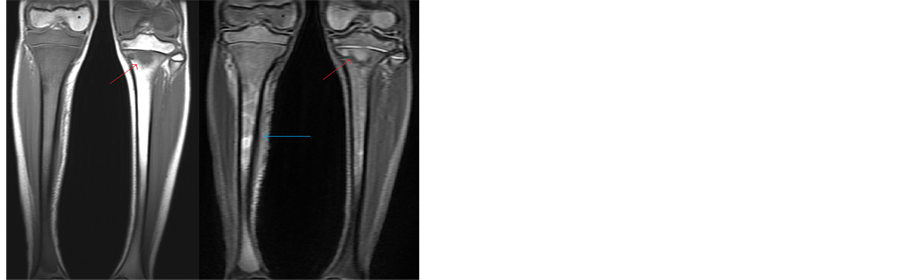

X-ray of the right tibia and fibula revealed circumferential cortical thickening and periosteal elevation of the tibia (Figure 1). MRI of the right leg showed abnormal T1 hypointensity and STIR hyperintensity in the entire length of the tibia marrow. Incidentally, there was abnormal T1 and STIR signal throughout the proximal left tibial marrow and left distal femur. A periosteal defect was seen anteromedially at the right tibial mid-shaft, correlating to the patient’s mass (Figure 2). A bone scan was subsequently performed showing multiple regions of abnormal marrow uptake: entire right tibia, mid and distal left femur, left femoral head and neck, and left tibial diaphysis (Figure 3).

Figure 2. MRI of bilateral legs. Denoted by the blue arrow is the periosteal defect in the right tibal shaft, correlating with the patient’s mass. Denoted by the red arrow is abnormal signal in the left tibia. The star marks normal bone signal in the right distal femur, as compared to the abnormal signal in the left distal femur.